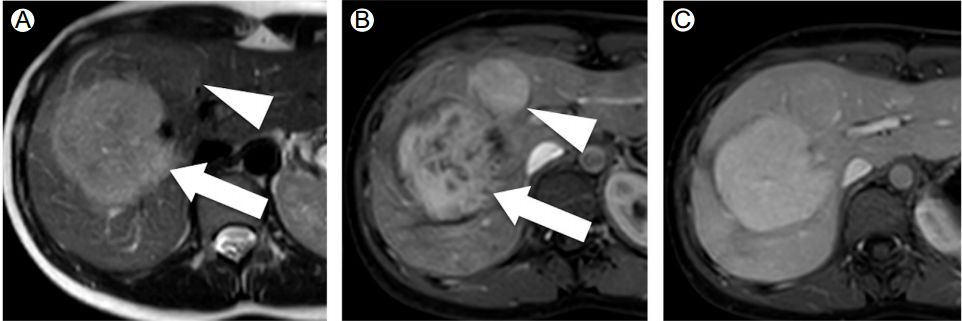

瘢痕的影像表现

上排为普通钆对比剂,中心瘢痕渐进性强化,随后呈低信号

下排为特异性对比剂,中心瘢痕渐始终强化不明显 医学百科网 | YxBaike.Com